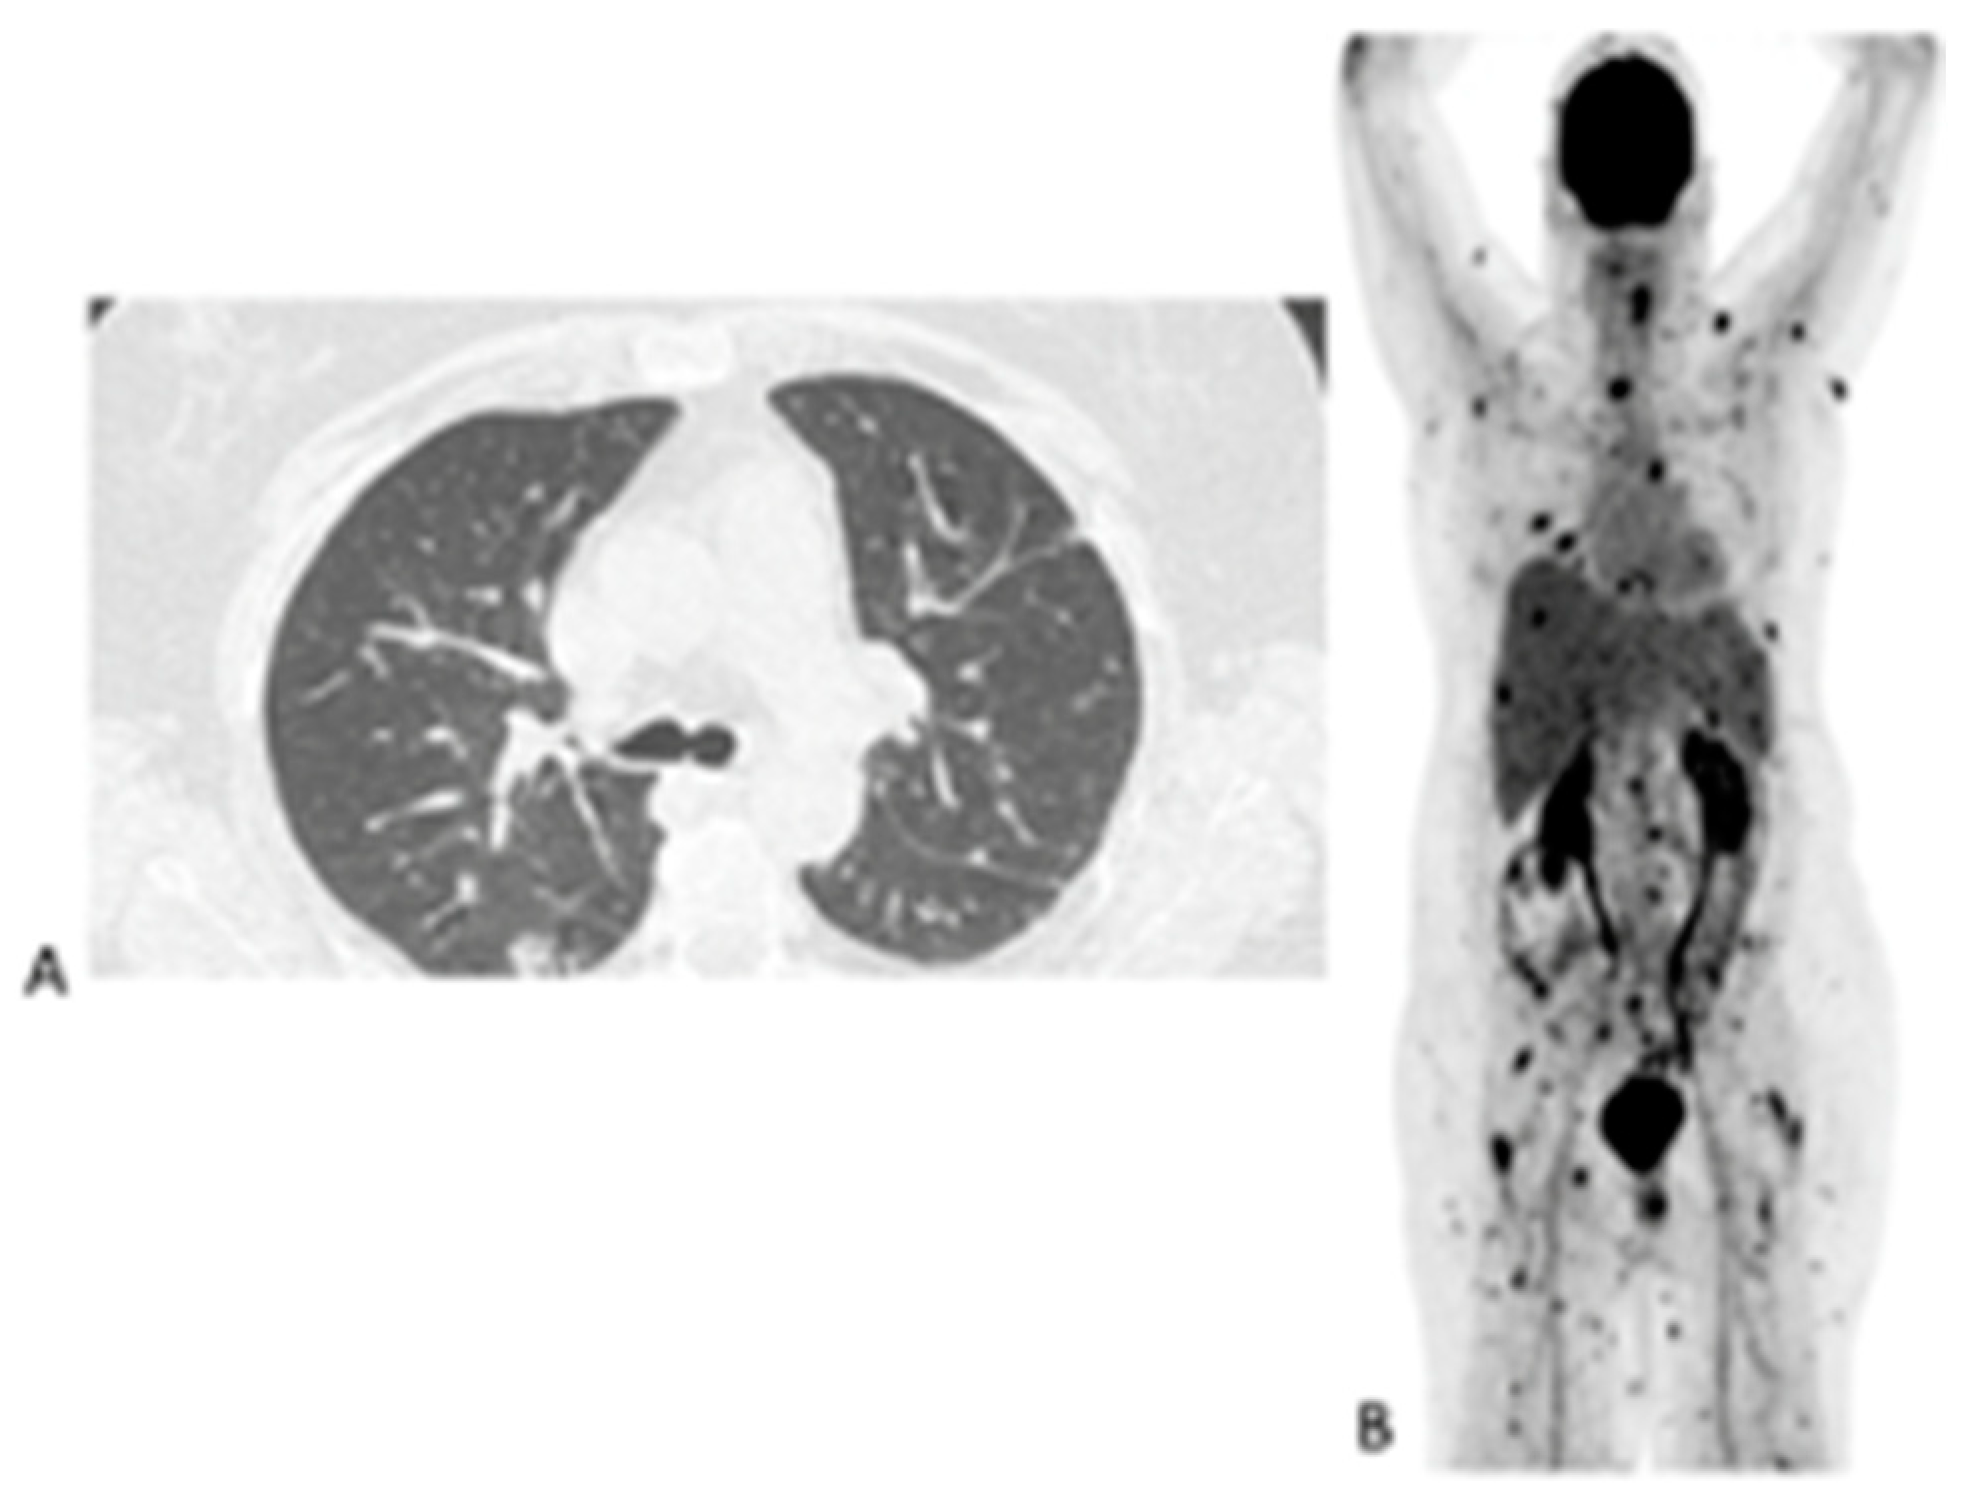

Figure 4.

Sixty-three-year-old female with acute myeloid leukemia on treatment for pulmonary aspergillosis. [18F]FDG PET/CT was performed because there was unexplained fever, and the IFI lesions seen on HR CT (A) were similar to in the HR CT scan performed a month and 2 months earlier. [18F]FDG PET/CT scan (B) showed multiple IFI lesions outside the thorax, providing an explanation for the persistent fever.